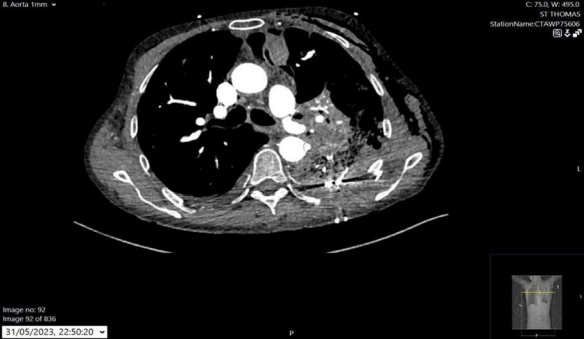

To achieve better long-term control of the aorto-pleural fistula, the patient subsequently underwent an urgent TEVAR (GORE® TAG® Conformable Thoracic Stent Graft, W. L. Gore & Associates (UK) Limited, Livingston, Scotland) (fig. 2b). After this procedure, the patient successfully underwent surgical unpacking of the chest 24 hours later, where no signs of active bleeding were found.

Fig. 2b X-ray showing TEVAR

Figure 3